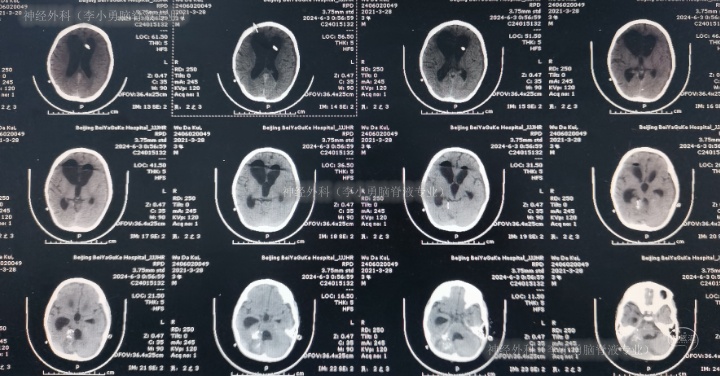

2024年6月3日(脑血管畸形栓塞术后脑积水伴间断高热5月余,外院经5次手术仍脑积水致严重颅内感染)转住入李小勇脑脊液专业,入院时:意识模糊,哭闹,咳嗽伴白色粘痰,高热,鼻饲流食;携带外院脑室外引流管;头部有多处瘢痕,有手术缝合线(图-4);入院时头颅CT示脑室外引流术后、脑积水(图-5)。

图-4:2024年6月3日入院时

图-5:2024年6月3日入院时头颅CT